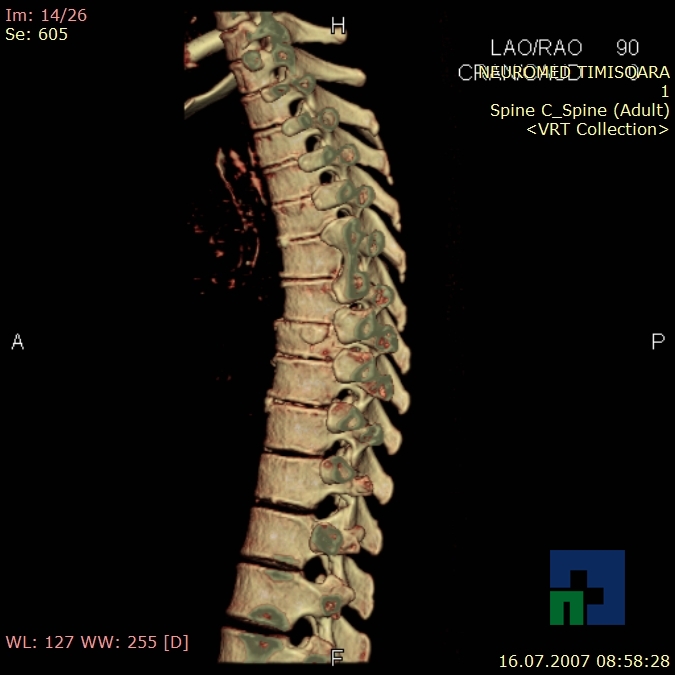

- Diagnosticul fracturilor:

- Unice

- Multiple

- Cu înfundare

- Complexe cranio-sinusale

- Complexe cranio-etmoidale

- Complexe cranio-orbitare

- Complexe cranio-faciale